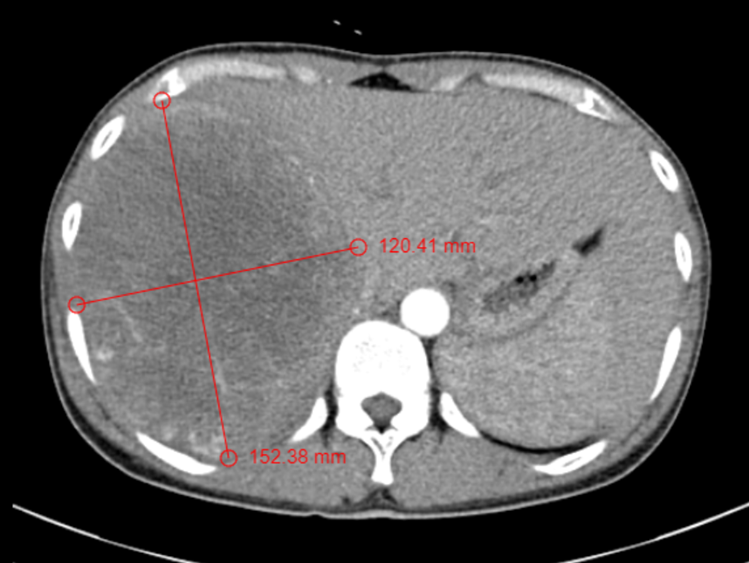

Hình ảnh CT-Scaner khối u gan lớn kích thước 12x15 cm

Bệnh nhân nữ 45 tuổi,tiền sử viêm gan B mạn không điều trị gì, vào viện vì đau tức vùng hạ sườn phải kèm gầy sút cân #4kg/ 2 tháng. Qua thăm khám và thực hiện các xét nghiệm cận lâm sàng, bệnh nhân được chẩn đoán ung thư gan nguyên phát với khối u gan kích thước lớn 12x15cm chiếm toàn bộ gan phải, chưa có hiện tượng xâm lấn mạch máu và di căn, chức năng gan còn đảm bảo. Bệnh nhân được chỉ định phãu thuật cắt toàn bộ gan phải và khôi u. Phẫu thuật đã được thực hiện thành công, an toàn. Hiện tại hậu phẫu ngày thứ 7 bệnh nhân ổn định, chức năng gan còn lại tốt, bệnh nhân đã tự ngồi dậy, vận động nhẹ nhàng.